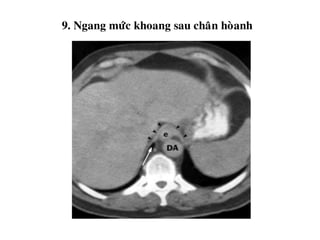

9. Khoang sau chaân hoaønh

9. Ngang möùc khoang sau chaân hoøanh